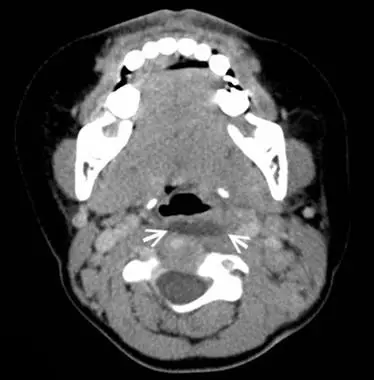

7歲男童因突發性高燒、吞嚥困難就醫,在對比劑注射後,接受電腦斷層掃描檢查如圖示,箭號所指病灶最可能診斷為何?

圖片為注射顯影劑後頸部軸位 CT,顯示:

- 咽喉後方(椎前)空間中可見一低密度(hypodense)集液病灶,位於中線略偏一側(箭號所指處)

- 病灶周圍可見環狀增強(ring enhancement),符合膿瘍壁的發炎性血管新生表現

- 病灶位於咽部後壁與頸椎椎體之間的咽喉後間隙(retropharyngeal space)

- 雙側頸部可見腫大淋巴結,顯影增強

- 氣道受壓,向前移位,是咽喉後膿瘍典型的繼發徵象

- 扁桃腺區域無獨立膿瘍形成,可與扁桃腺周膿瘍(peritonsillar abscess)區分

上述 CT 表現(咽喉後間隙低密度集液 + 環狀增強 + 氣道前移)高度符合咽喉後膿瘍。